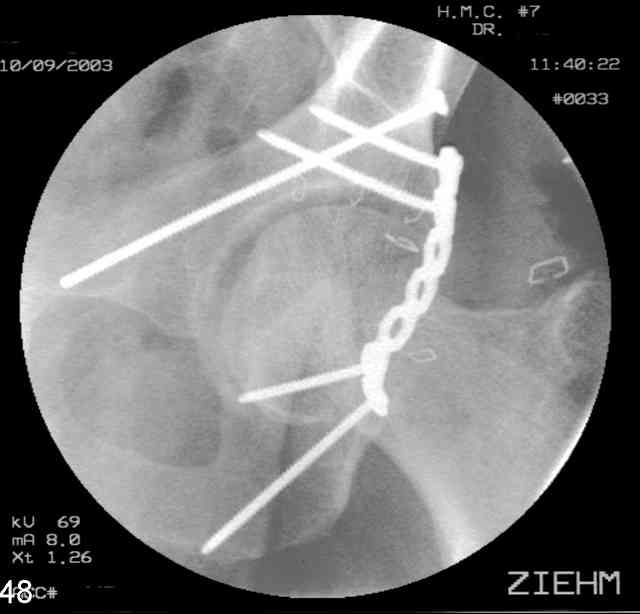

Here's a pic from the foot of the bed and you can see the clamp in the wound and the knee is extended so he must've had a tight rectus. The C-arm is rolled back to an obturator oblique image to reveal the anterior column...we put a slight outlet tilt to combine the images and give a better view of the anterior column...we can see the posterior column limb reduction in the wound, we can palpate the quadrilateral surface limb, and the image demonstrates the anterior column portion...you can adjust the tilt and rotation to image tangentially to the fracture plane if you'd like. We've inserted a 2mm K wire to site the starting point and aim/orientation for the drill and screw

Prone Imaging

same image, just another look.